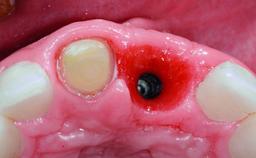

A 32-year-old female Caucasian patient with a compromised maxillary right central incisor was referred to us by a general dentist. Her chief complaints were discomfort and mobility of tooth 11 with unsatisfactory esthetics due to discoloration. The patient reported a previous trauma, some years earlier, as the origin of pathology on the afflicted tooth. Anamnesis was negative for any other dental or periodontal pathology in the remaining dentition. The patient did not take any medication and reported to be a light smoker (5–10 cigs/day). She had high esthetic expectations of her treatment. The extraoral examination revealed a high smile line with full exposure of her maxillary teeth and surrounding soft tissue in the area between the second premolars.

Case Type Single-Tooth Space

Jaw Maxilla

Area Anterior

# of Teeth 1

# of Implants 1

Defining Characteristics One missing tooth to be replaced by an implant-borne prosthesis